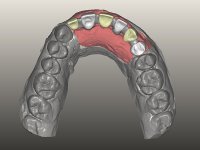

O paciente foi observado conjuntamente e a dúvida que surgiu de imediato foi se seria possível com a regeneração óssea a efectuar poder ser reabilitada naturalmente a zona das papilas interdentárias. Nesse sentido foi feito um enceramento de diagnóstico que contemplaria as duas hipóteses, utilizando ou não a cerâmica gengival. A confecção desse enceramento foi fundamental para expor ao paciente a dificuldade da reabilitação. O wax-up deu origem a um mock-up que foi aprovado pelo paciente e que simultaneamente serviu de guia imagiológica. O caso foi planificado cirurgicamente e realizada uma guia cirúrgica com que foram colocados os implantes. Após 10 semanas foi feita a 1ª impressão para confecção da ponte provisória. Foram criados os primeiros perfis de emergência na gengiva artificial e foi digitalizado o modelo. Por processo de CAD-CAM foi confeccionada uma ponte provisória aparafusada baseada no enceramento de diagnóstico. A ponte trabalhou durante 8 semanas os tecidos moles que foram fielmente copiados numa impressão com técnica de moldeira aberta. Os transferes foram individualizados com resina composta para copiarem fielmente os perfis de emergência criados pela ponte provisória. Confeccionado o modelo de trabalho definitivo, foi realizada uma infra-estrutura em zircónio seguindo a orientação do enceramento de diagnóstico. O assentamento da infra-estrutura foi testado em boca e simultaneamente foi novamente impressionados os tecidos moles com um silicone fluido. Nessa consulta foi feito o levantamento da cor. Os dentes 13 e 23 apresentavam uma saturação anormalmente forte que resolvemos não valorizar, optando por privilegiar a relação com o sector antero-inferior. Foi realizada uma nova gengiva artificial com a impressão que acompanhou a impressão de arrasto com a infra-estrutura. Após a colocação da cerâmica na infra-estrutura foram coladas as meso-estruturas. O trabalho final foi aparafusado lentamente permitindo a adaptação dos tecidos moles.